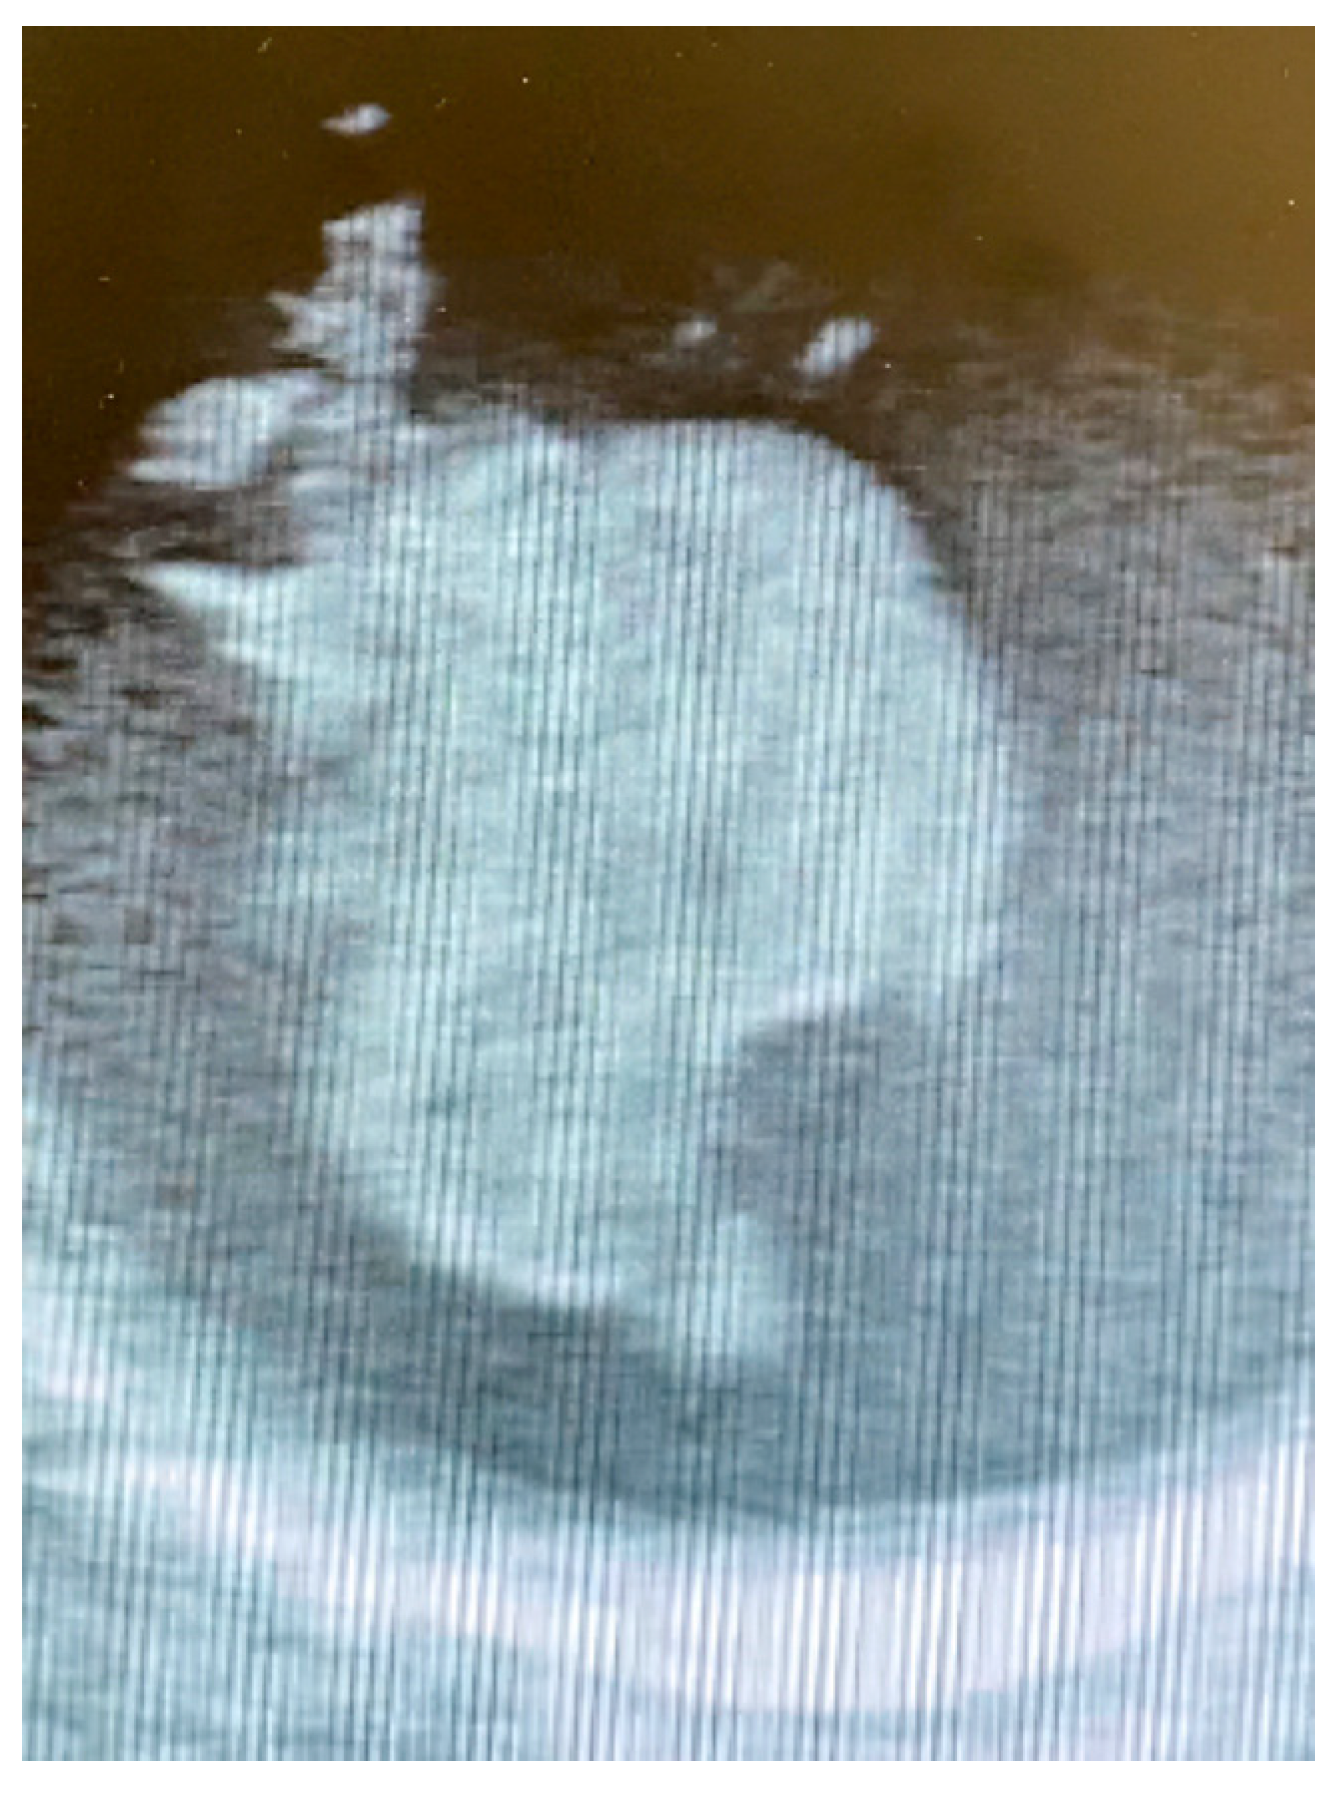

2. Case Presentation